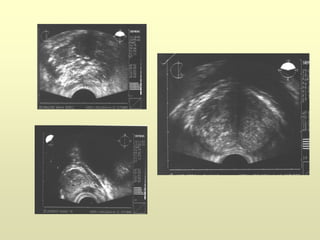

ETR y Biopsia

Estadificación

T2: tumor localizado dentro de la próstata

T3a: Tumor que afecta la cápsula

T3b: Invasión de vesículas seminales

T4: invasión de órganos adyacentes (recto, vejiga…)